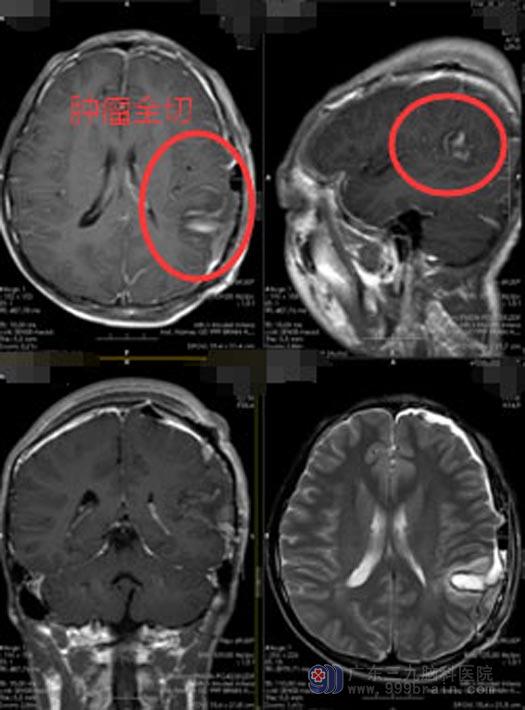

完善相关检查后,鲁明带领治疗团队为阿康行“左侧颞顶叶占位切除术”。神经功能导航准确定位,术中避开语言区、脑电图定位癫痫灶,将肿瘤全切并同时切除了癫痫灶。

术后,阿康生命体征平稳,神志清醒,四肢活动自如,对答清晰。无癫痫发作,语言功能正常。术后病理为节细胞胶质瘤。

本病例涉及到语言区,通过术前功能磁共振预测出语言区和肿瘤的位置关系,术中利用神经功能导航,结合病人意愿行术中麻醉唤醒手术,避免不可逆的语言功能损伤。为了取得更好的癫痫控制率,本病例不仅切除了神经节细胞胶质瘤,也将周围的致痫灶一并切除,从而使得患者得到满意的治疗效果。